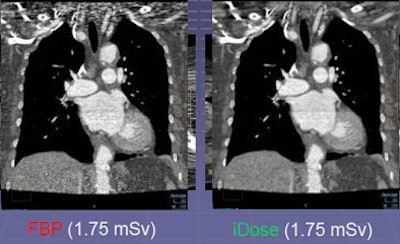

In contrast, the iDose algorithm (Philips Healthcare, Andover, MA) that Mendel described in his ISCT talk uses an iterative method designed to reproduce the look of full-dose filtered back projection (FBP) at a much lower dose using an iterative method. The goal is to allow use of a higher percentage of iterative reconstruction while maintaining a clinically acceptable image.

First, the projection data itself are denoised with the application of a Poisson denoising algorithm. Then in the pixel space, iDose compares the image to a noiseless ideal anatomical model, enabling noise reduction with an appearance that is very similar to the full-dose image and does not shift the noise spectrum significantly, Mendel said.

"So even at 80% dose reduction, the images are virtually identical" to a full-dose image, even when the images are rendered, he said. In contrast, the first-generation systems show major shifts in the noise spectrum, sharpening edges and blurring other structures compared to standard images.

The key aspect of iDose is that it maintains the noise power spectrum (thus the appearance) of a full-dose image while utilizing high levels of dose reduction, Mendel said.